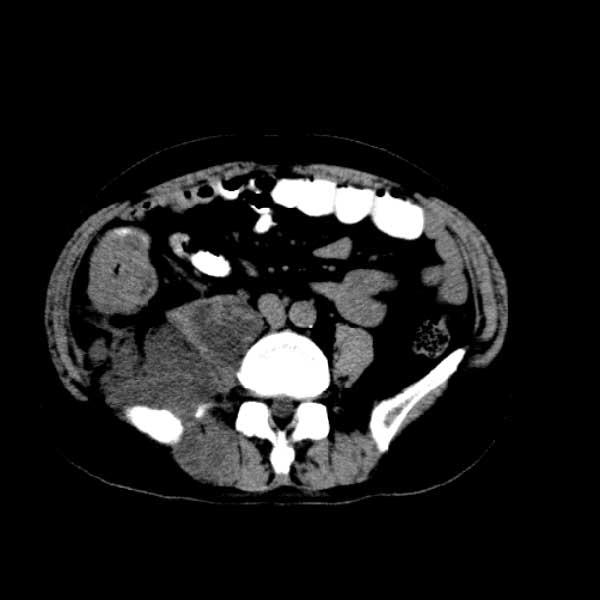

标题: CT13513:男 71 腹部疼痛20余天,近几天高热就诊,骨窗未见异 [打印本页]

标题: CT13513:男 71 腹部疼痛20余天,近几天高热就诊,骨窗未见异

考虑感染性病变可能性大,起源于阑尾?

感染,脓肿形成

考虑为化脓性阑尾炎.脓肿形成.及多肌肉累及.

考虑右侧腰大肌脓肿,向右髂窝、右腹股沟流注。

支持化脓性阑尾炎伴右髂窝脓肿、腰大肌腰方肌脓肿形成。

考虑腹腔及盆腔化脓性炎症,累及右侧髋关节及腹股沟区.

首先考虑化脓性阑尾炎伴腰大肌、腰方肌脓肿,不除外回盲部结核。

回盲部癌待排除。

患者肠镜检查考虑结肠癌,病理证实

患者肠镜检查考虑结肠癌,病理证实。肺部ct可见多发结节,考虑转移